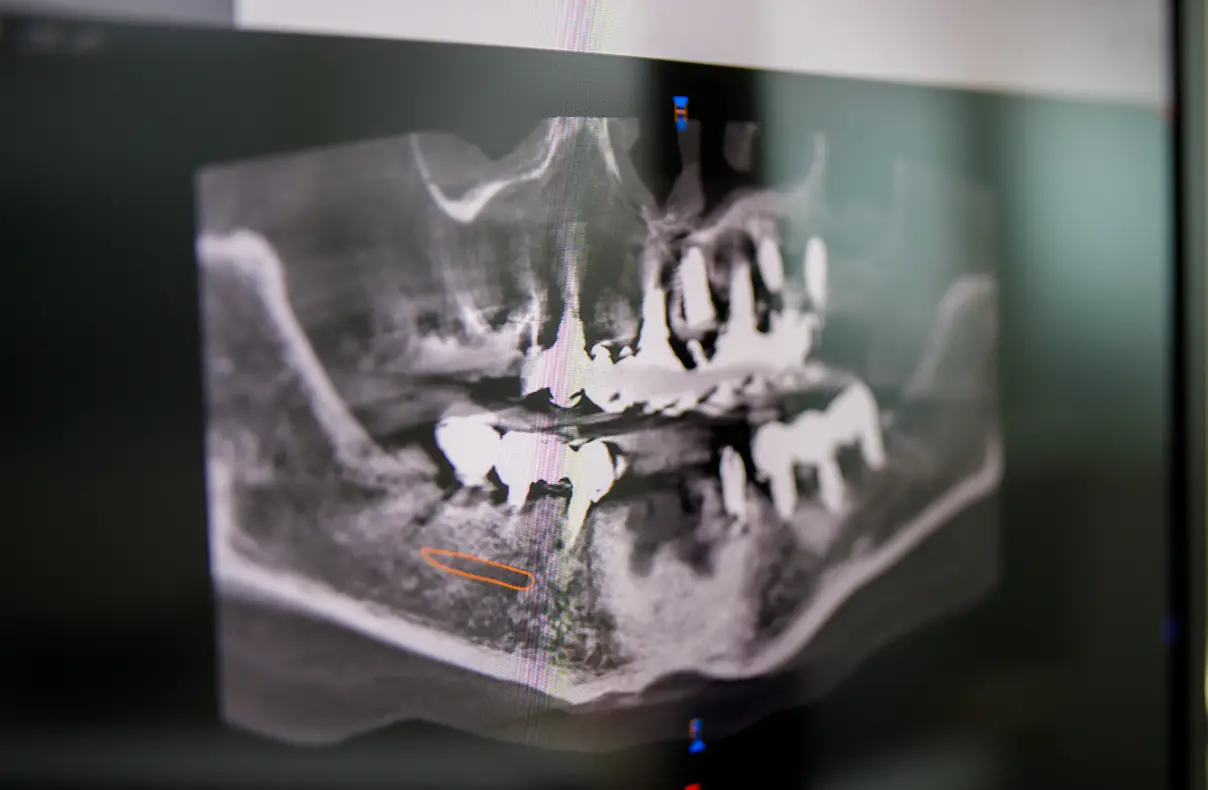

診療内容に関係なく、検査の際は歯科用CTで撮影して、より精密な3Dデータをもとに診療いたします。歯科用CT撮影は自費診療で行なう検査ですが、患者様により適切な治療を提供するために無料で実施しています。

虫歯や歯周病、インプラント、矯正など病気や治療法への不安や疑問はお気軽にご相談ください。検査結果をもとに、患者様の歯の状態と合わせてお答えします。また、ご希望の方にパノラマレントゲン写真をプレゼントしています。